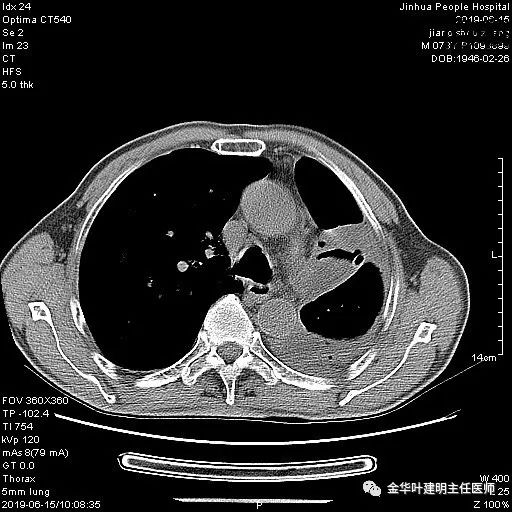

考虑左侧大量胸腔积液,遂进一步胸部CT检查:

以上是肺窗表现,下面为纵隔窗影像: